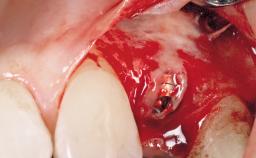

A 30-year-old female patient had lost tooth 21 and was referred to our clinic for consultation and treatment. Due to advanced apical infection, tooth 21 had been extracted two months earlier at another clinic and an acrylic-resin tooth had been bonded to the adjacent teeth. The patient desired implant treatment to avoid any damage to the adjacent natural teeth. While the patient had no history of any systemic disorder, she was a heavy smoker and exhibited medium to advanced periodontitis in the entire jaw. After the initial treatment to achieve a pocket probing depth of less than 4 mm and no bleeding on probing, a decrease in the height of the papillae mesial and distal to the extraction site and overall gingival recession were observed.

Type of Implants One-Piece|Reduced-Diameter

Bone Augmentation Horizontal|Staged

Augmentation Materials Autogenous chips|Membrane